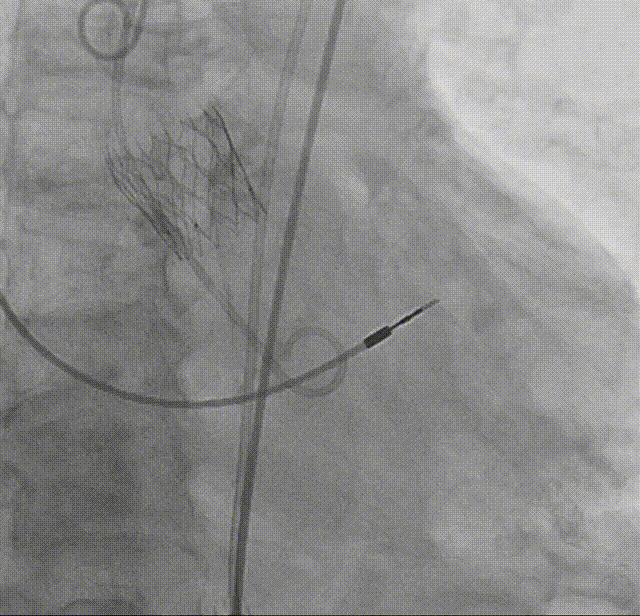

输送系统顺滑过弓

瓣下1mm初始定位

瓣膜释放至全展开位

全展开位评估:锚定区呈直筒状,瓣架中段微收腰,瓣膜形态佳